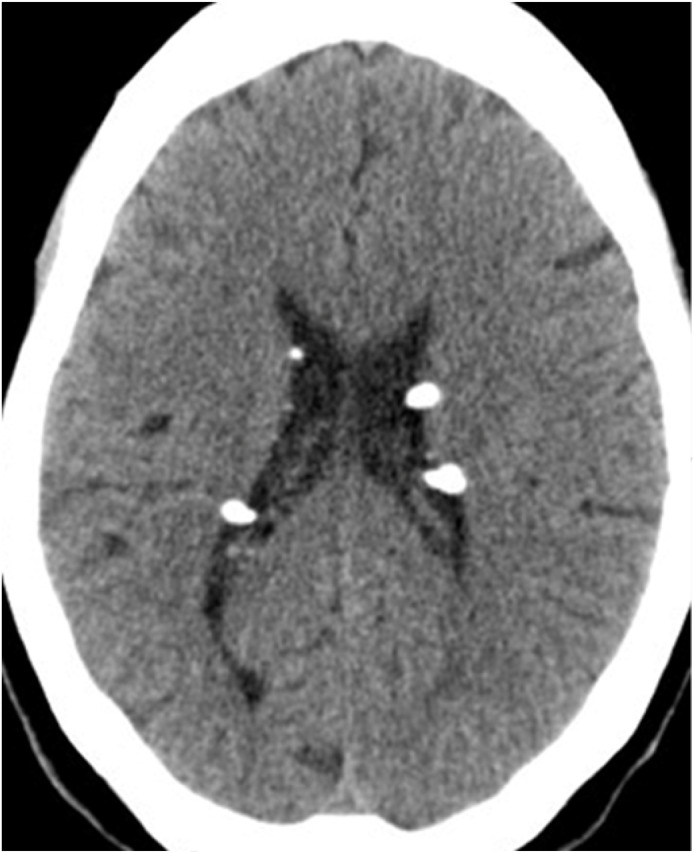

The Multifaceted Nature of Tuberous Sclerosis Complex.